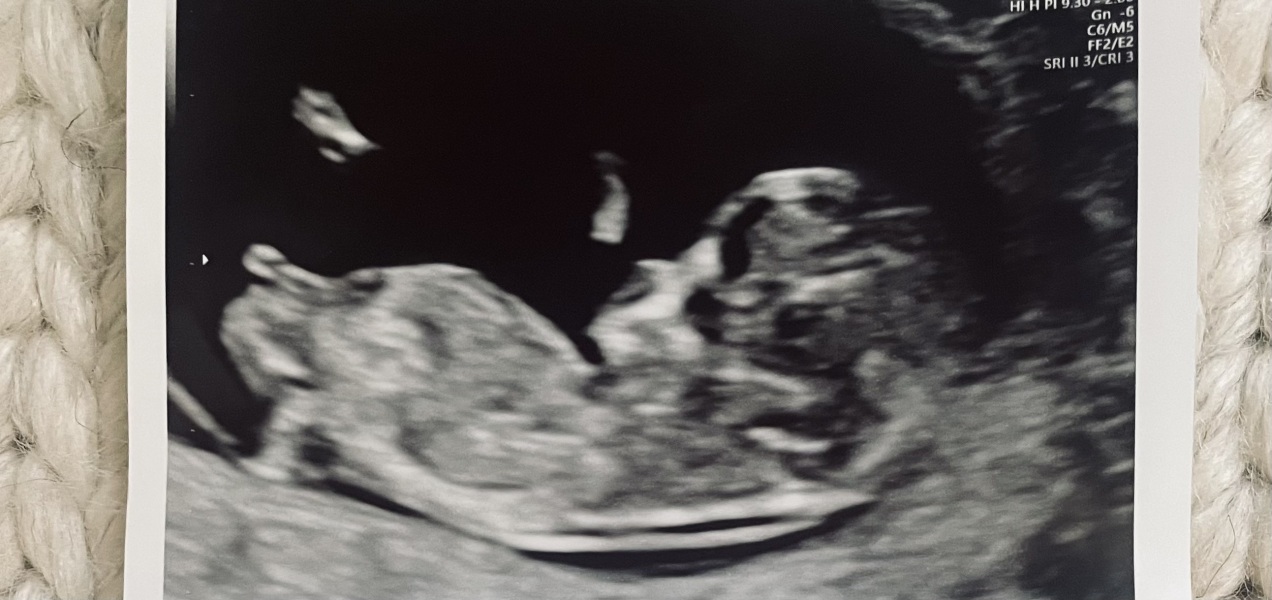

Boy or Girl - Nub Theory

hjw6991 · 13/03/2024 15:51

I'd love to know your thoughts on what you think!

Jamontoast1 · 14/03/2024 20:09

I’d say girl!